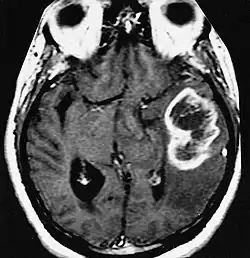

MRI showing a ring-enhancing lesion in the brain of a patient with glioblastoma multiforme

A ring-enhancing lesion is an abnormal radiologic sign on MRI or CT scans obtained using radiocontrast. On the image, there is an area of decreased density (see radiodensity) surrounded by a bright rim from concentration of the enhancing contrast dye. This enhancement may represent breakdown of the blood-brain barrier and the development of an inflammatory capsule. This can be a finding in numerous disease states. In the brain, it can occur with an early brain abscess as well as in Nocardia infections associated with lung cavitary lesions. In patients with HIV, the major differential is between CNS lymphoma and CNS toxoplasmosis. CT imaging is the appropriate next step to differentiate between the two conditions.[1]